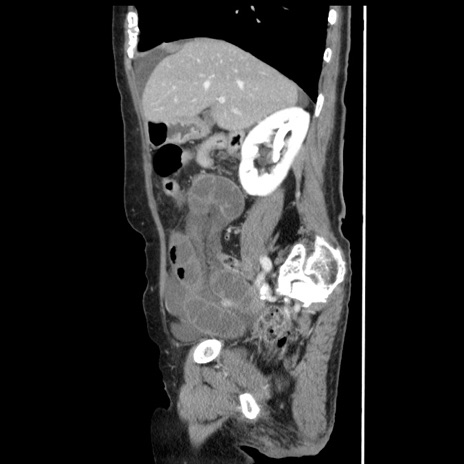

冠状断像

【症例】80歳代女性

【主訴】腹痛

【現病歴】8時間前から腹痛あり来院。

【既往歴】糖尿病、脂質異常症、子宮体癌にて子宮全摘術

【身体所見】意識清明・会話良好だが腹痛で苦悶様、全腹部にわたって反跳痛と圧痛あり

【データ】WBC 13600、CRP 0.14、LDH 224、CK 90